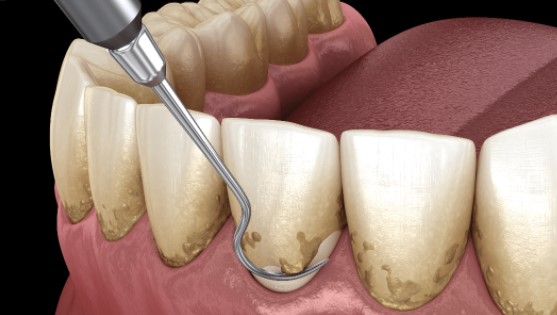

Osnovni oblik liječenja je parodontna kiretaža ili kako je mi volimo zvati “kupovina vremena”. To je osnovni način pomoći na kratki rok odn. nekoliko godina, dok se kao dugotrajnije riješenje djeluje na uzročnik problema i može se odlično ukomponirati sa svim vrstama umjetne kosti i tkivno vođenom regeneracijom, laserom i terapijom ozonom.

Parodontološka kiretaža zuba

- Detaljna parodontološka kiretaža (dubinsko čišćenje paradonta po regiji/kvadrantu) 250€

- Detaljna parodontološka kiretaža (dubinsko čišćenje paradonta jedna čeljust) 500 €

- Detaljna parodontološka kiretaža (dubinsko čišćenje paradonta obje čeljusti-gornja i donja) 900 €